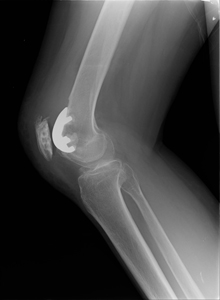

(2)膝蓋大腿関節置換術

膝の皿(膝蓋骨)と大腿骨との間の軟骨が消失し、他の部分の軟骨が残っている場合に適応があります。

正面

側面

軸写図14:術前レントゲン像

側面図15:部分置換(膝蓋骨)術後レントゲン像